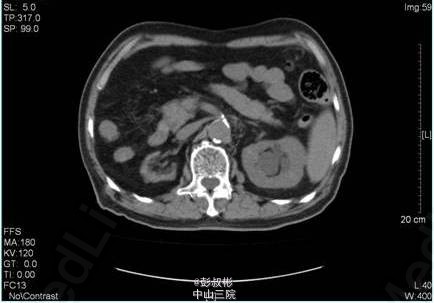

1、主诉:腹胀、纳差、少尿、伴双下肢乏力1周 2、既往史:有"陈旧性脑梗塞、广泛脑白质变性、高血压病(3级极高危)、双下肢动脉硬化、帕金森氏综合征、脂肪肝、慢性胆囊炎、右肾萎缩、痛风性关节炎史,十年前因"肾结石"行手术治疗,具体不详。

3、辅助检查:血常规:血红蛋白浓度116. g/L。生化十项:尿素氮26.110mmol/L,肌酐(酶法)736.000umol/L。泌尿系彩超,右肾慢性肾功能不全声像,右肾缩小;左肾代偿性增大可能,肾窦内隐约见引流管回声。CT:右肾萎缩,左输尿管上段结石。

4、入院后处理:完善相关检查,考虑存在泌尿系梗阻引起的肾功能不全,于03-14行“B超引导下经皮肾穿刺造瘘术”, 03-16 复查生化十项:肌酐(酶法)151.000umol/L,尿素氮11.190mmol/L。3-15 3-18 KUB:盆腔左上部见一结节状高密度影,大小约为7mm×7mm。左肾区可见造瘘管影。 3-18于手术室全麻下行“左侧输尿管镜下钬激光碎石术”,术程顺利,术后予抗感染、补液、营养支持等对症治疗。于03-19复查生化十项:尿素氮6.550mmol/L,肌酐(酶法)103.600umol/L。复查KUB提示结石已清除,左肾造瘘管及双J管在位。